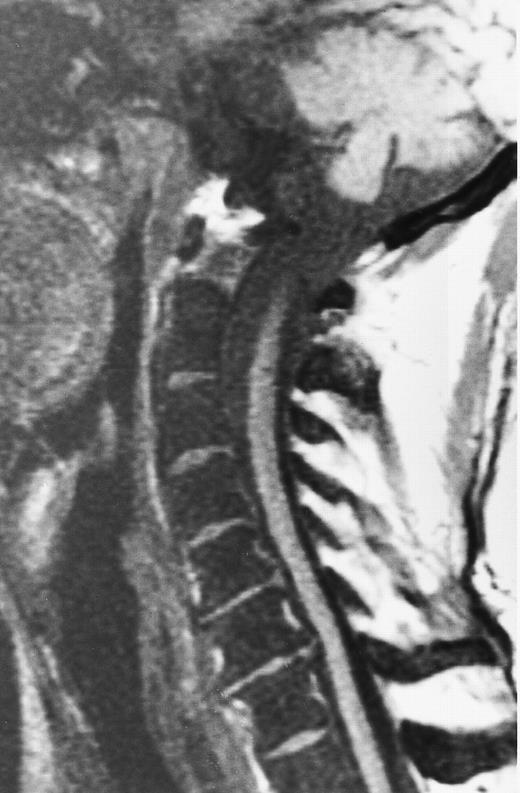

An 82-year-old man with multiple myeloma and cord compression. T2-weighted, fat-suppressed fast spin echo (5000/96, TR/TE, ET16) sagittal MR image of the thoracic spine shows abnormal signal in several compressed vertebral bodies (arrows). The spinal cord (c) is severely compressed by epidural mass (m).